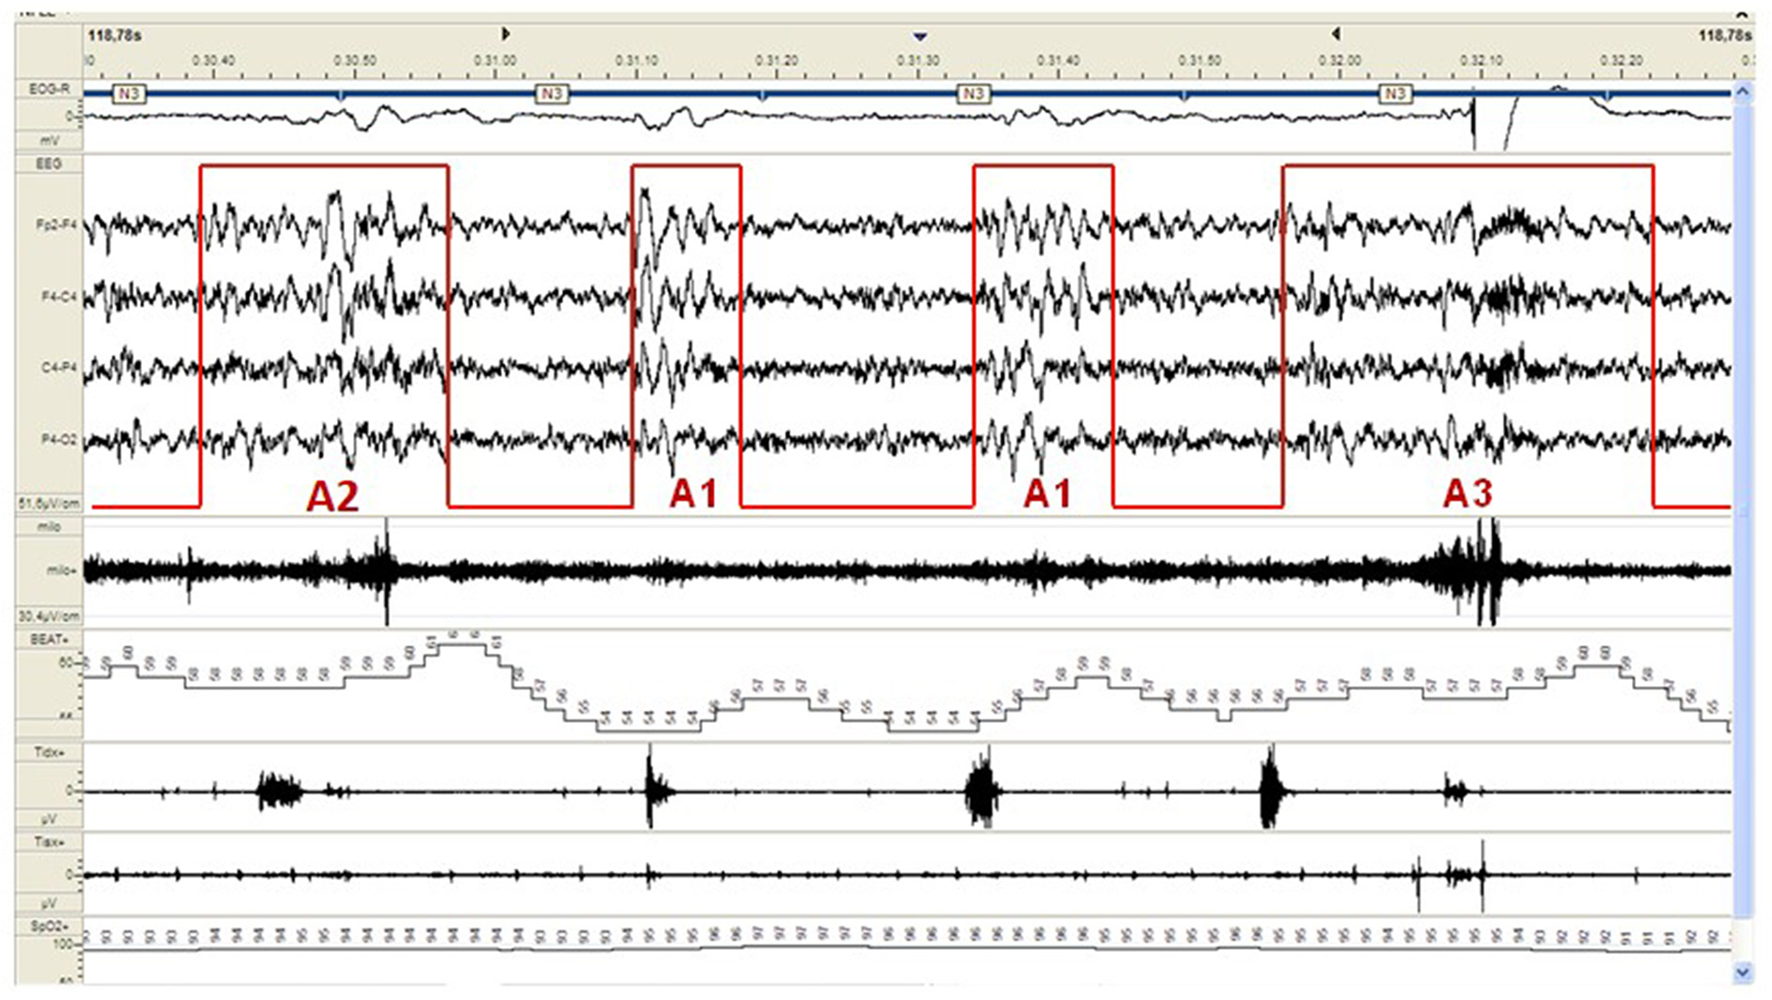

CAP represents a pivotal component of the dynamic sleep structure and can be considered a polysomnographic hallmark of sleep instability. CAP is organized in cycles, with subsequent cycles composing a CAP sequence. Depending on the presence or absence of CAP cycles, sleep itself can be divided into “CAP sleep” and “non-CAP sleep”. Each CAP cycle can be subdivided in a phase A (activation phase) and a following phase B (de-activation phase). Phase A can be further classified in three subtypes: A1, A2 and A3, according to reciprocal proportion of slow waves and fast rhythms (see Figure 2). The distinction is not trivial as CAP subtypes A1 typically boost SWS and reinforce sleep propensity, whilst CAP subtypes A2 and A3 usually translate a tendency toward REM sleep and/or prepare the brain for an awakening. The utilization of CAP metrics ensures a deeper understanding of sleep kinetic troughtout the night, however, as CAP analysis is highly demanding and time-consuming, not all the sleep laboratories can guarantee its measurement in everyday clinical practice.

Figure 2

Example of a CAP sequence (CAP phases A highlighted in red) during stage N3 of NREM sleep in a patient affected by periodic limb movement disorder (PLMD). Note that the more disturbing leg movements (right part of the figure) are associated with CAP subtype A3. CAP subtypes A1 have a milder cardiovascular impact.